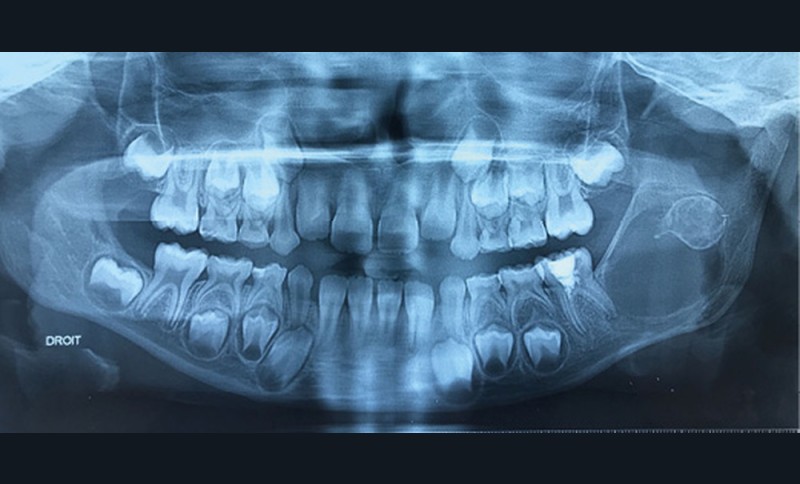

Les kystes et tumeurs bénignes osseuses maxillaires ou mandibulaires chez l’enfant sont le plus souvent asymptomatiques. Ces lésions osseuses sont découvertes de façon fortuite lors d’un bilan radiographique de routine réalisé par l’odontologiste pédiatrique ou l’orthodontiste [1-3]. Néanmoins, des lésions peuvent parfois se développer rapidement et être destructrices [1, 2]. Certains signes cliniques spécifiques à la chronologie de l’éruption dentaire chez l’enfant doivent nous alerter tels qu’un retard d’éruption dentaire ou une éruption dentaire asymétrique (fig. 1). D’autres manifestations cliniques, moins spécifiques à l’enfant, peuvent également orienter le clinicien sur la présence d’une pathologie osseuse sous-jacente : mobilité dentaire, douleur, tuméfaction, limitation de l’ouverture buccale, trouble neurosensoriel, etc. [3]. C’est la radiographie panoramique qui va ensuite mettre en évidence/confirmer la présence d’une lésion intra-osseuse (fig. 2).

La radiographie panoramique permet une première interprétation de la lésion osseuse (localisation, nombre, taille approximative, etc.). Cet examen est souvent complété par un bilan d’imagerie en trois dimensions de type Cone Beam [4]. Il précisera le volume et les limites de la lésion ainsi que ses rapports avec les structures anatomiques avoisinantes (tableau 1). Ces données radiologiques confrontées à l’examen clinique et à la fréquence relative des lésions permettent de réaliser un diagnostic d’intuition qui orientera la prise en charge.